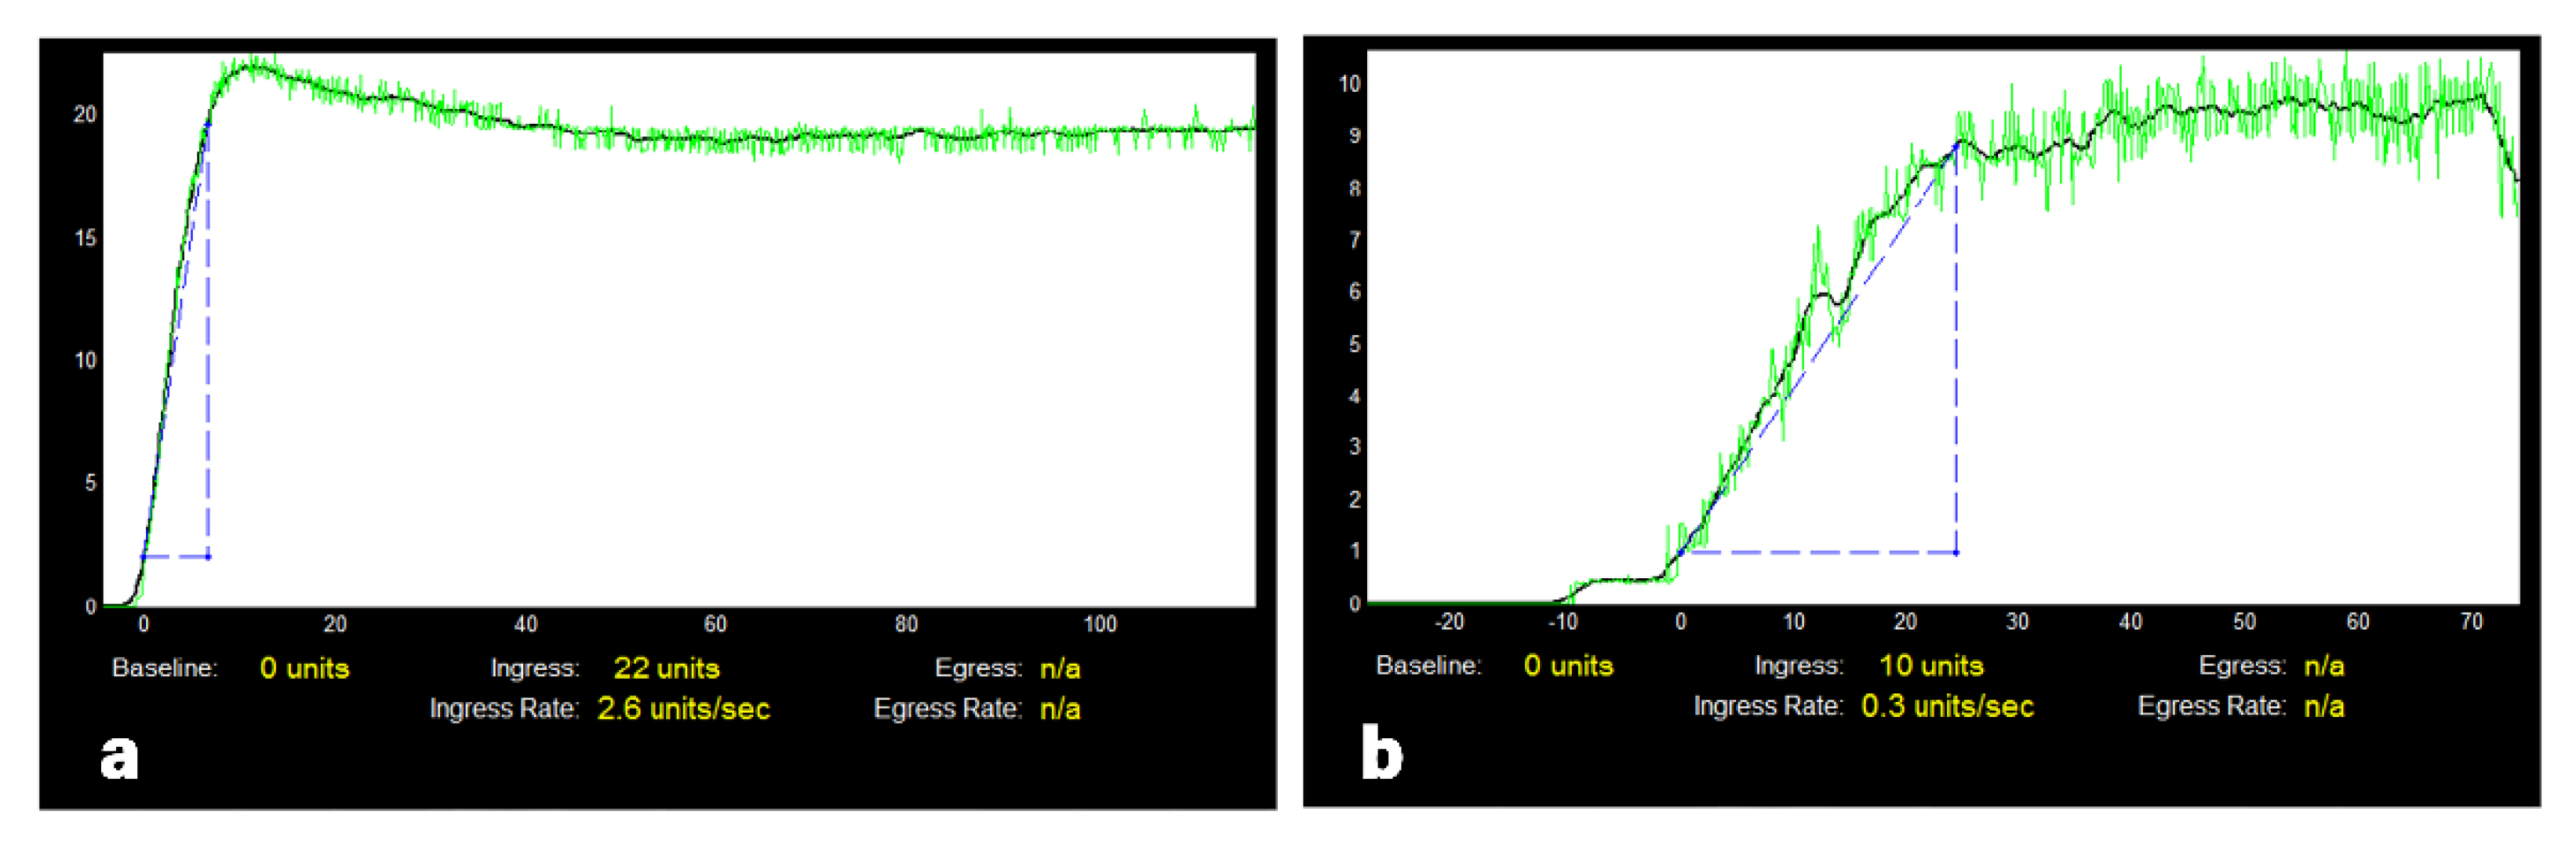

2.3. Analysis of Fluorescence Angiography Video Sequences and the Ureteral Perfusion

3.5. Intraoperative Kidney Allograft Perfusion Analysis

3.6. Correlation of Ureteral Perfusion with Kidney Perfusion

3.7. Association between Intraoperative Perfusion Analysis and Ureterovesical Anastomosis Complications